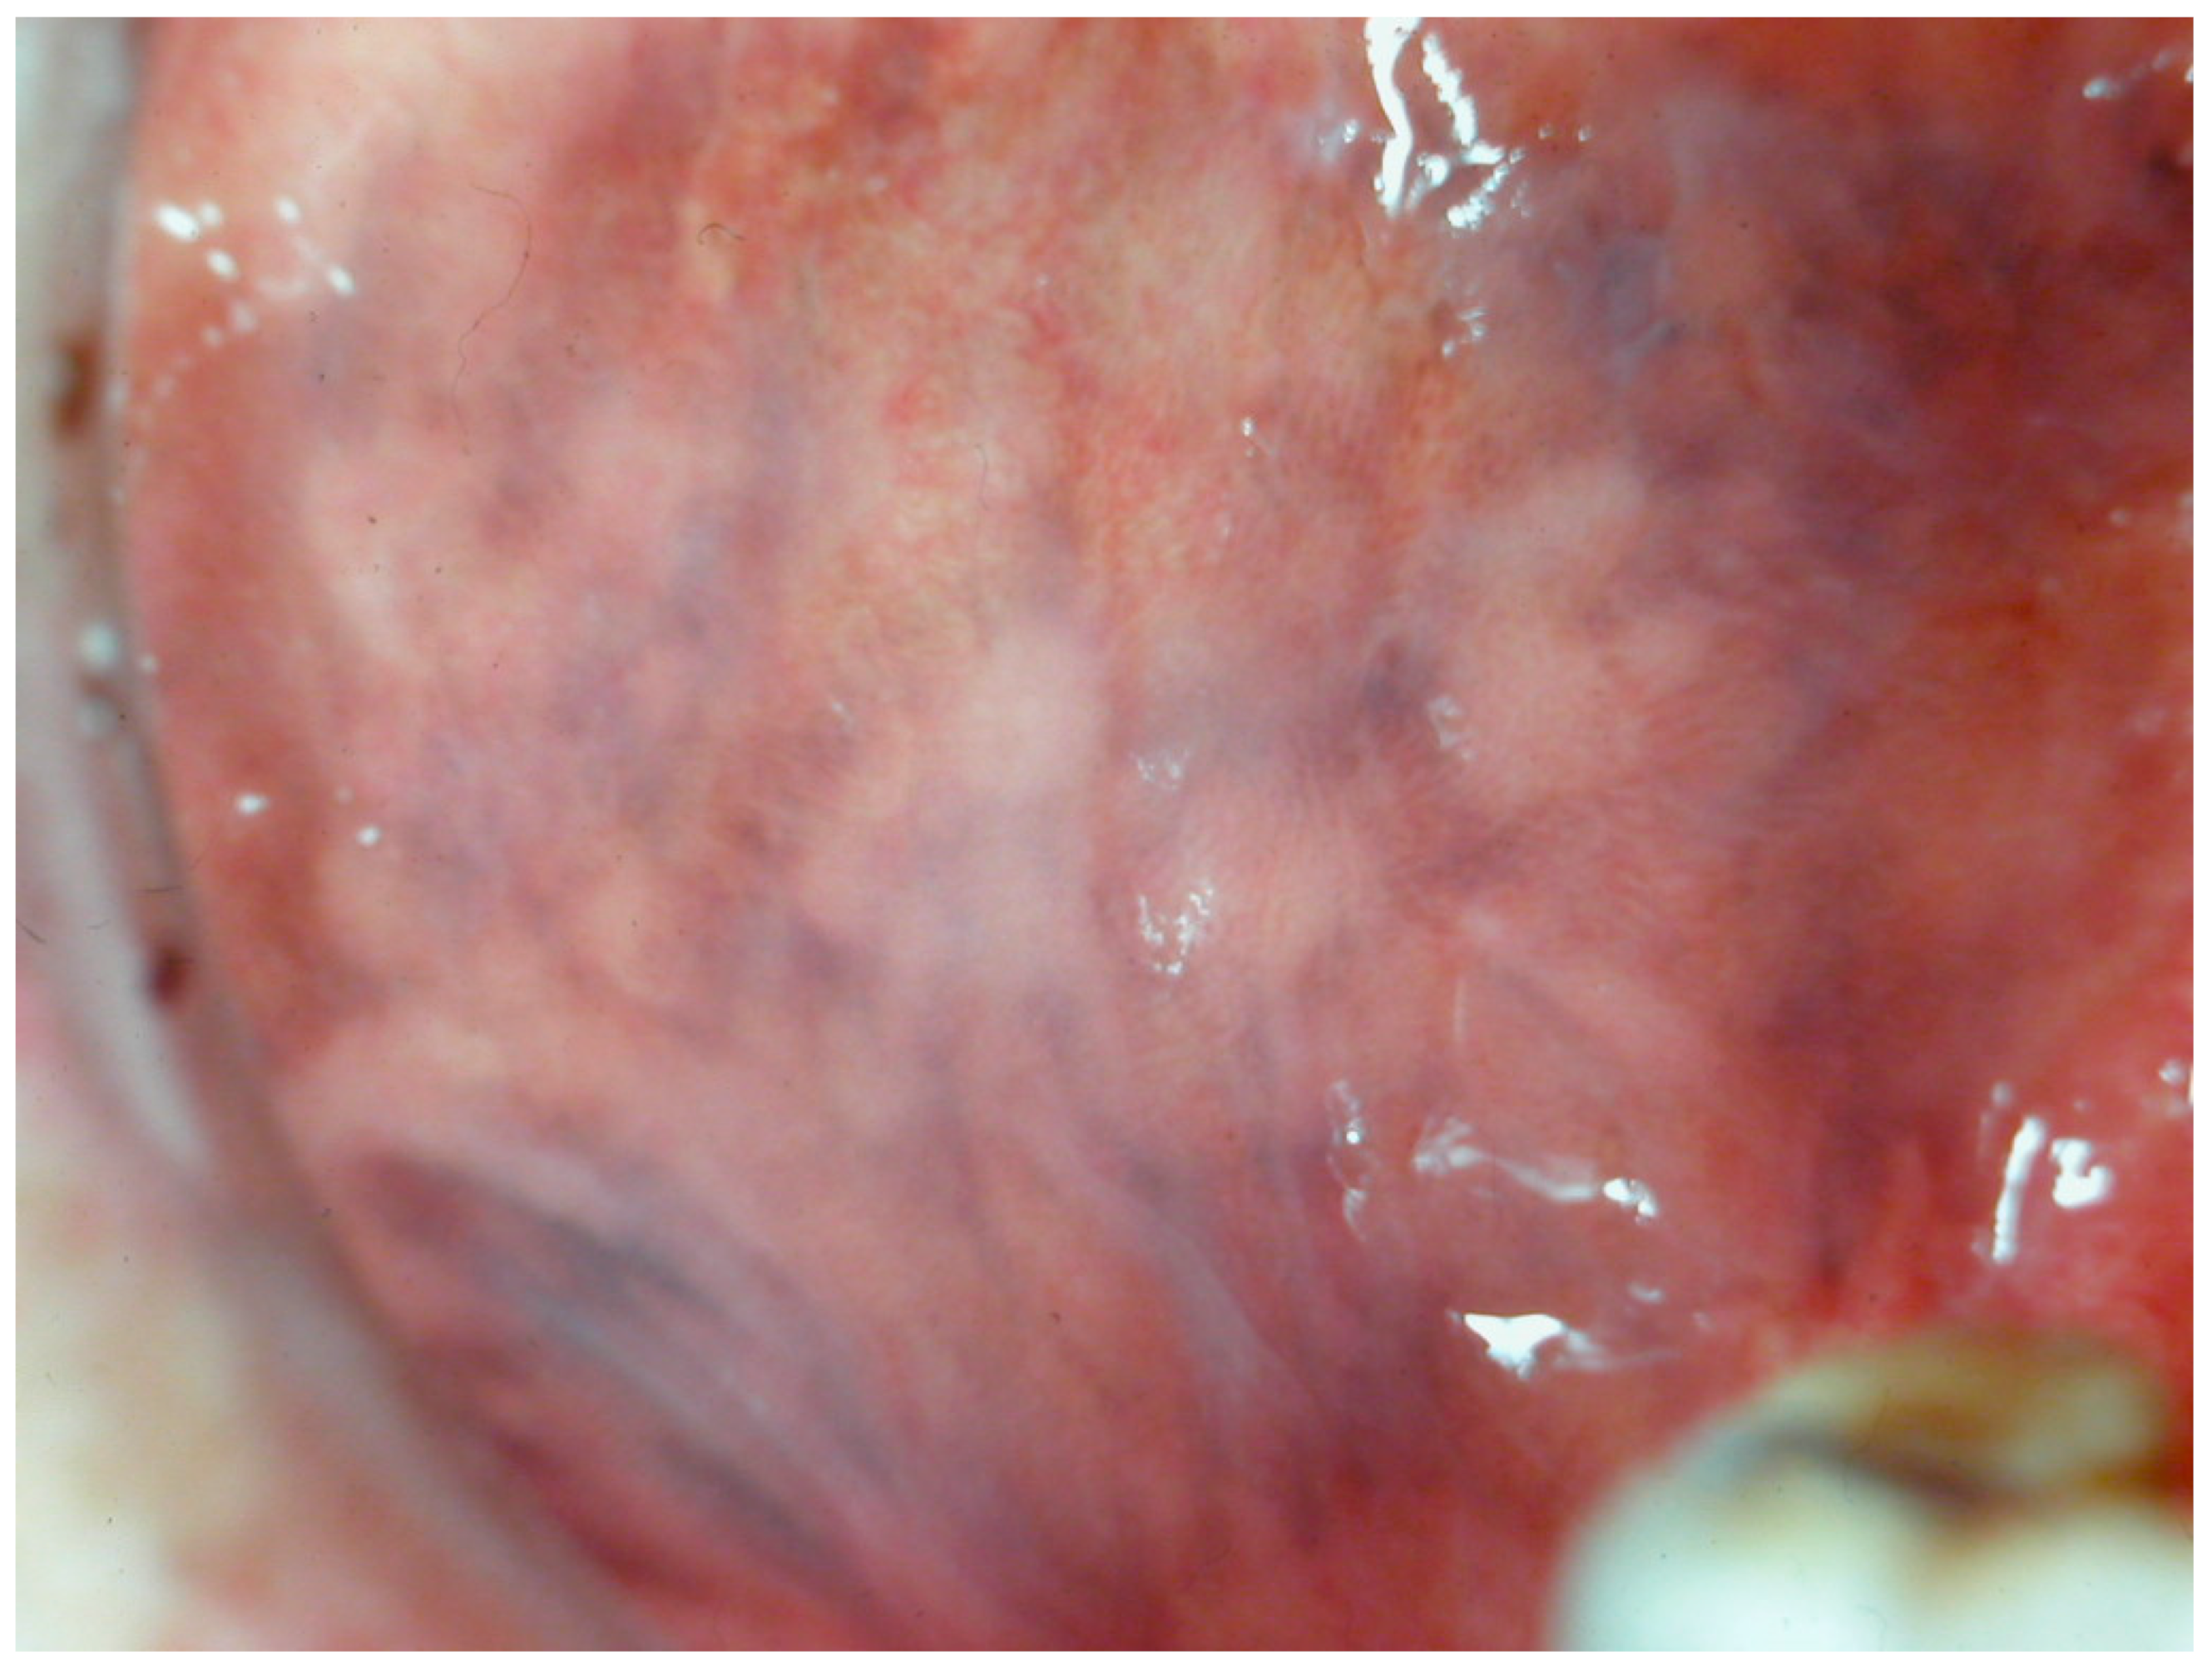

Among the various forms of lichen planus, there exists a distinct pigmented variant known as lichen planus pigmentosus (LPP). This variant was first identified in India by Bhutani et al. in 1974, who introduced the term to describe its unique presentation. LPP is distinguished by its slow onset and the appearance of small, dark brown or black macules that typically emerge on sun-exposed areas of the skin (Figure 12). Over time, these macules can merge to form larger patches of hyperpigmentation. Although LPP primarily impacts the face, torso, and upper limbs, LPP rarely involves the oral mucosa. Notably, the condition does not affect the palms, soles, or nails [84,85].

Figure 12.

Area of tongue mucosa pigmentation in a patient with reticular oral lichen planus in a 42-year-old male patient. Patient refers to these lesions as being present for several years. (archive S.A., patient signed the consent for clinical pictures).

Histologically, LPP exhibits notable atrophic alterations in the epidermis, vacuolar degeneration of the basal cell layer, and melanin incontinence within the dermis. This is further accompanied by the presence of dispersed melanophages and a sparse infiltrate around hair follicles or blood vessels. This pigmented variant shows considerable histopathological overlap with erythema dyschromicum persistant, though differences in clinical presentation and immunologic features suggest they may be distinct entities. Despite this, some dermatologists debate whether these conditions should be considered separate diseases [86,87].